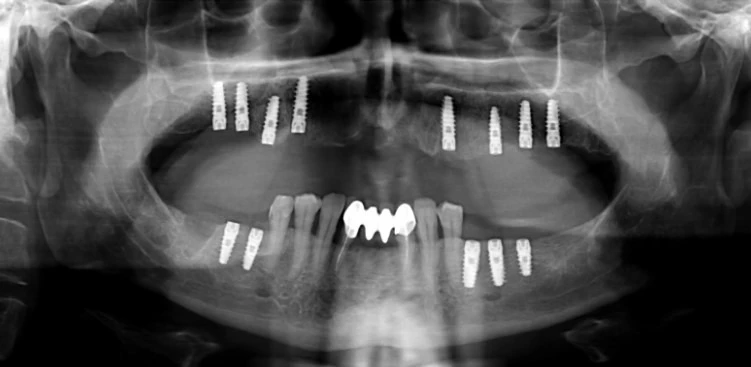

Сүйек тініне орнатылған имплант табиғи тіс түбірінің қызметін атқарады. Ол шайнау кезіндегі жүктемені сүйекке беріп, тіннің табиғи жаңару процестерін ынталандырады және оның жұқаруына жол бермейді. Осы арқылы сүйек тінінің биіктігі мен тығыздығын сақтап, беттегі деформациялардың алдын алуға және көрші тістердің саулығын қорғауға мүмкіндік туады.

Алматы тұрғындары үшін, белсенді өмір салты мен сырт келбетке қойылатын жоғары талаптар маңызды болғандықтан, имплантация тек жоғалған тістерді қалпына келтіру тәсілі ғана емес, жасқа байланысты өзгерістердің алдын алу әдісі ретінде де қарастырылады. Заманауи имплантациялық жүйелер жоғары биосәйкестікке қол жеткізуге, қабыну қаупін азайтуға және көптеген жылдарға тұрақты нәтижеге мүмкіндік береді.

Имплантацияның тиімділігі көп жылдық клиникалық тәжірибелермен және пациенттердің пікірлерімен дәлелденген. Алматыда бұл процедураға сұраныстың жоғары болуы оның әмбебаптығына байланысты: импланттар бір тісті де, бірнеше тісті де алмастыруға мүмкіндік береді және ең күрделі клиникалық жағдайларда да толық функционалдылықты қамтамасыз етеді.